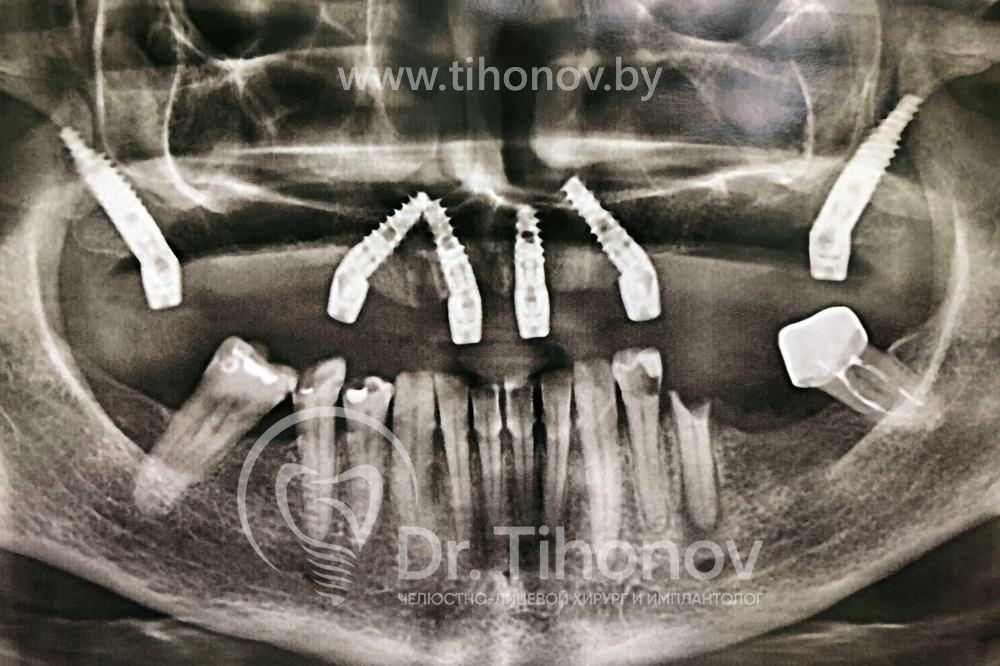

В процессе проведения операции на верхней челюсти были удалены оставшиеся разрушенные корни зубов, одномоментно установлены 6 имплантатов и на 5-й день зафиксирован в полости рта функциональный и эстетичный металлопластмассовый протез. Таким образом, удалось обойтись без дорогостоящих длительных процедур наращивания костной ткани и подарить пациентке красивую улыбку всего за 5 дней.